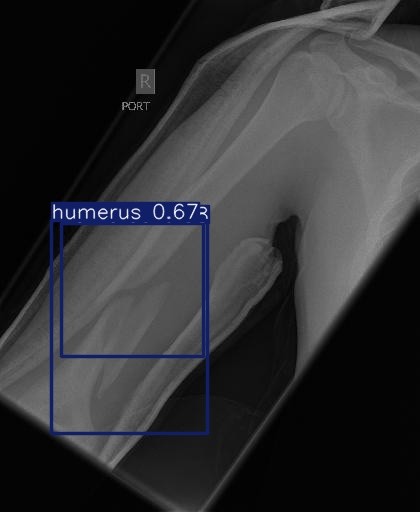

Fracture Detection & Localization

Detect Fractures in Real-Time

Analyze X-rays in real-time to detect fractures and highlight them with Box

Flag potential fracture zones and generate visual overlays to assist radiologists during diagnosis.

We build deep learning models for fracture detection using custom YOLOv8 and Grad-CAM for best result and great accuracy.